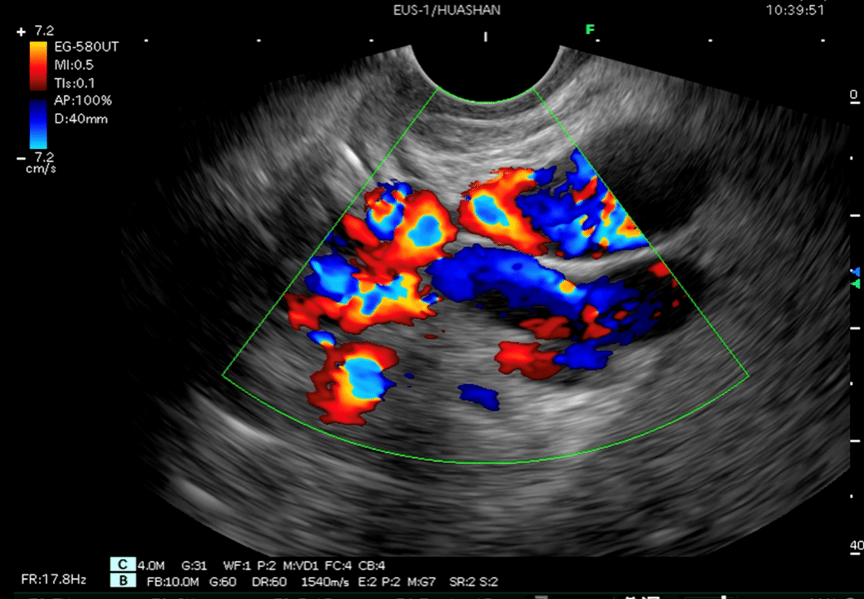

本次手术由消化内科史海涛副主任、马师洋副教授、赵菊辉副教授及袁佳医师组成核心术者团队,依托超声内镜系统,创新性采用"弹簧圈骨架支撑+组织胶生物封堵"双联疗法。术中使用多普勒超声实时导航技术,精确定位大小为3×2.5cm的曲张静脉团块。通过预载式FNA穿刺系统,将医用级钛合金弹簧圈精准植入曲张血管腔道形成物理支撑,继而注入医用组织胶与聚桂醇复合制剂,在血管腔内形成稳定的生物-机械复合栓塞体。与传统内镜治疗方法相比,该术式具有显著优势。一方面,能够借助超声多普勒实时评估血流动力学变化,实时监测手术进程,最大程度规避误穿风险;另一方面,持久的栓塞效果有效降低了再出血率,同时巧妙地规避了异位栓塞风险,极大减少了术中出血风险,为患者的生命安全提供了更有力的保障。